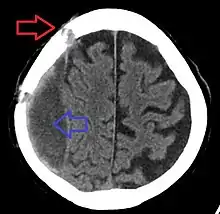

Subdural hematoma as marked by the arrow with significant midline shift

A subdural hematoma demonstrated by CT

It is important that a person receive medical assessment, including a complete neurological examination, after any head trauma. A CT scan or MRI scan will usually detect significant subdural hematomas.

Subdural hematomas occur most often around the tops and sides of the frontal and parietal lobes.[3][2] They also occur in the posterior cranial fossa, and near the falx cerebri and tentorium cerebelli.[3] Unlike epidural hematomas, which cannot expand past the sutures of the skull, subdural hematomas can expand along the inside of the skull, creating a concave shape that follows the curve of the brain, stopping only at dural reflections like the tentorium cerebelli and falx cerebri.

On a CT scan, subdural hematomas are classically crescent-shaped, with a concave surface away from the skull. However, they can have a convex appearance, especially in the early stages of bleeding. This may cause difficulty in distinguishing between subdural and epidural hemorrhages. A more reliable indicator of subdural hemorrhage is its involvement of a larger portion of the cerebral hemisphere. Subdural blood can also be seen as a layering density along the tentorium cerebelli. This can be a chronic, stable process, since the feeding system is low-pressure. In such cases, subtle signs of bleeding—such as effacement of sulci or medial displacement of the junction between gray matter and white matter—may be apparent.